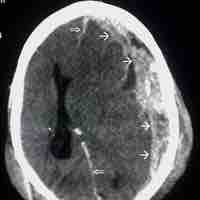

Traumatic Brain Injury

Traumatic brain injury (TBI) occurs when an external force injures the brain and can be caused by a direct impact or by acceleration alone.